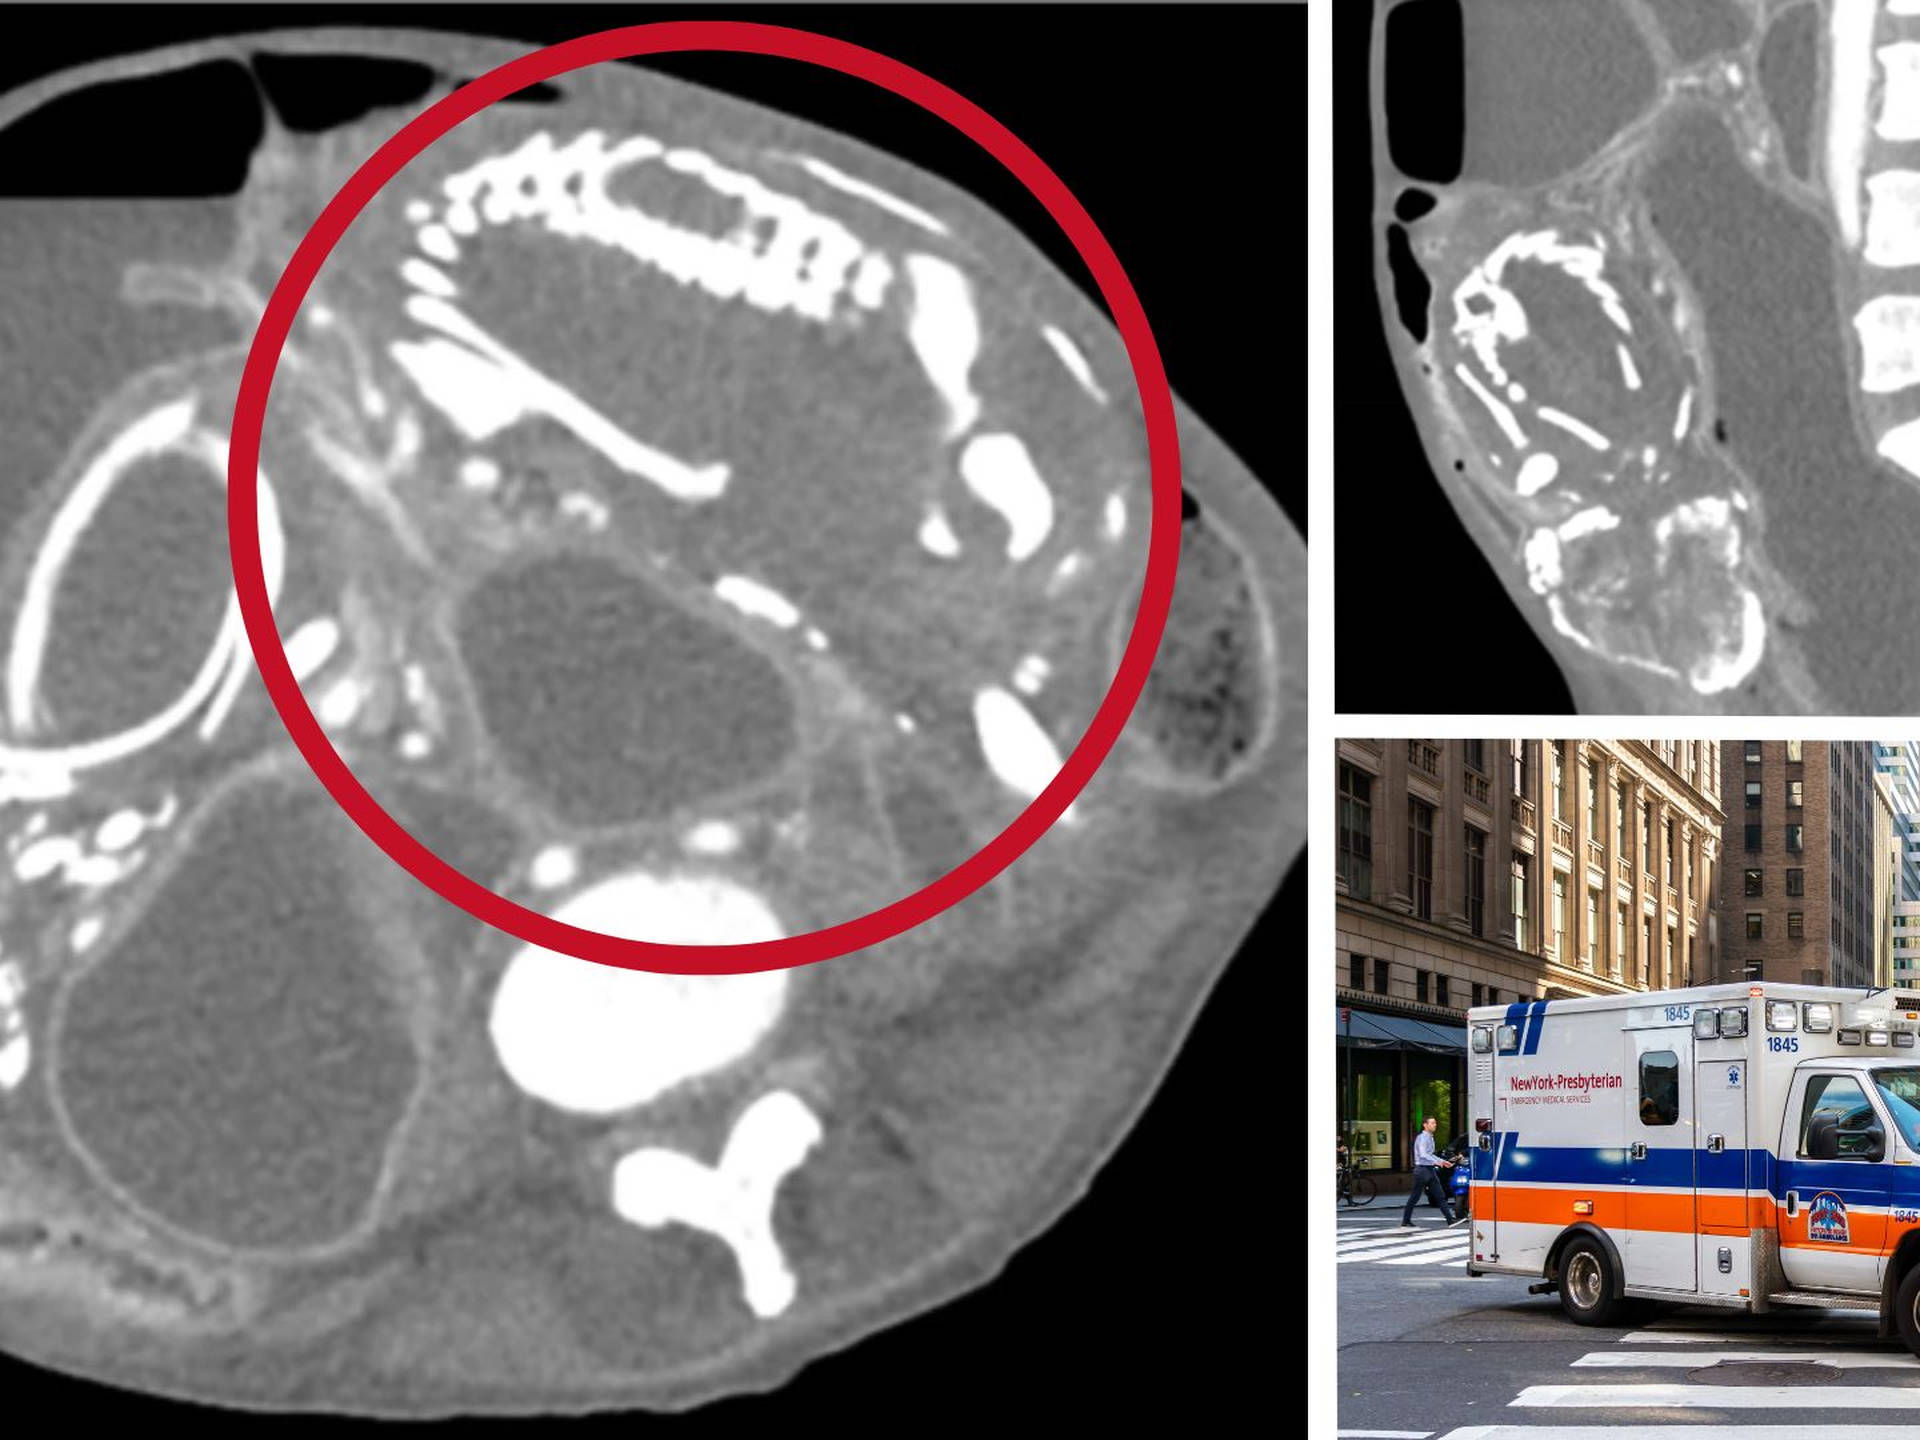

(这位难民女性的腹部扫描)

根据CT扫描的发现,她的腹中有一个长15-20厘米的石胎,能清晰看到胎儿的骨架。因为石胎体积较大,压迫了她的诸多脏器,导致了一系列健康问题。

(一名埃塞俄比亚女性的石胎扫描,该石胎已在她体内20年。)